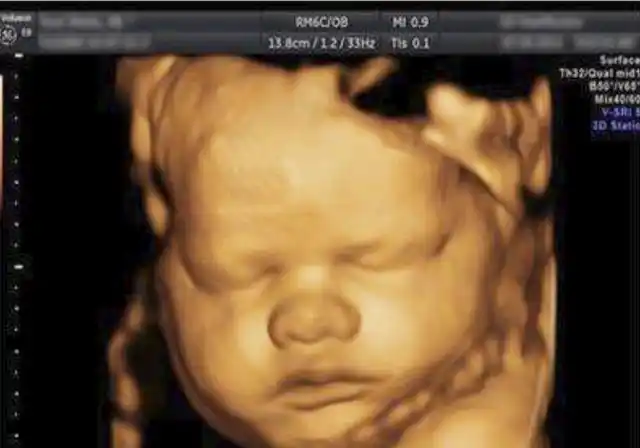

胎宝四维照片丑哭那生出来会不会丑看完之后孕妈就能放心了

被宝宝的四维彩超照丑哭了?不是医生技术不好,而是有客观原因的

四维彩超回来,感觉宝宝好丑啊!

你第一次看到宝宝的四维彩超照片是什么感觉

四维彩超通过,感觉好丑,第一次没照到脸,走了半小时才照了这么一张